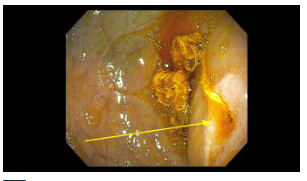

Endoscopy findings: There was a narrowed opening (different orientation of same narrowing in both pictures) with a string-like material.

Surgical findings: A duodenal web with a piece of lint was identified. The patient had a laparoscopic wedge excision with a transverse closure of the duodenotomy. The lint may have occluded the tiny opening of the web that he had been living with since he was born.

My take: This is the first time I have seen the endoscopic appearance of a duodenal web.